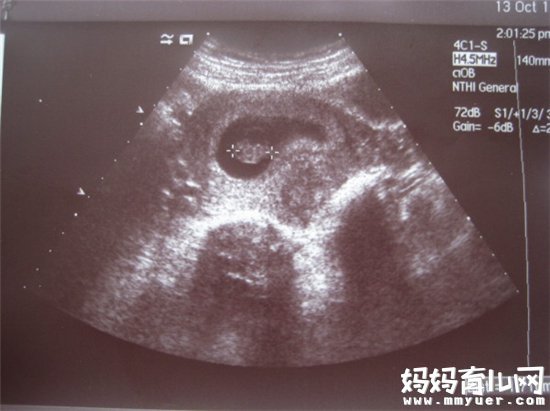

在胚胎发育的早期胚芽时就可通过B超看到心管搏动,最早可以在6-8周(自停经时算起),如果10周还未检测到心管搏动,在排除了末次月经可能记错了日期的情况下可以诊断胚胎停止发育,就像自然界中所有的物种存在的优胜劣汰一样,可能是本身种子质量问题无法发育成功。